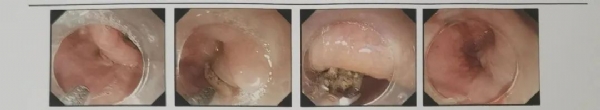

8月4日晚,一阵急促的电话铃声在脾胃病一科护士站响起,一位中年患者在吃饭时,将鸡骨头误吞进去,咽喉部出现了异物感,医生安排患者行胸部CT检查,发现异物卡在左侧梨状窝处,情况紧急,如果尖锐的异物进入胃和肠道,会出现出血或穿孔等并发症。